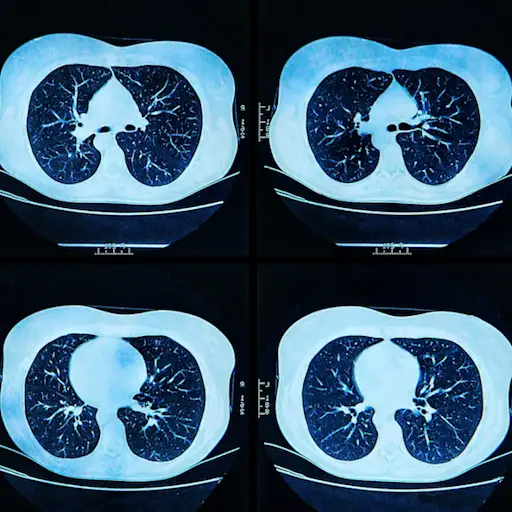

接受任何形式的健康新闻是焦虑的,尚Gowrinathan说,医学博士,一位精神病医生专攻psycho-oncology圣约翰癌症研究所普罗维登斯圣约翰医疗中心在圣莫尼卡,还有这个过程本身,而每三个月到一年一次,可以可怕:“PET, CT和MRI机器不是最友好的地方,”她指出。“它们发出很大的噪音,而且很局促。”当然,最大的触发因素是,扫描可能是你最初是如何得到癌症诊断的,以及你如何知道它是否复发。

瓦查尼医生说,对于那些没有被诊断出肺癌的人来说,尽管发现癌症的风险相对较低,屏幕还是会产生焦虑。他说,幸运的是,与某些癌症不同,肺癌对何时停止使用屏幕有明确的指导。如果检查下的病变是实心的(模糊了肺的基础结构),他们只需要定期扫描两年。有一小部分看起来比较模糊,可能需要仔细观察2到5年。所以,当你的护理团队建议结束检查时,请深呼吸并同意。